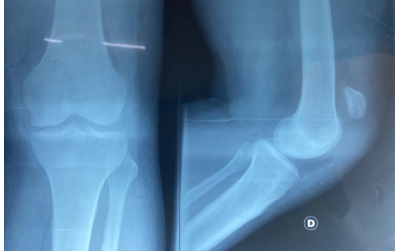

Mr. , a 43-year-old man with no medical history, presented 2 months after a domestic accident with an old injury to the left knee. He had slipped on the stairs and initially consulted a traditional healer. Examination revealed loss of active knee extension and a palpable gap along the patellar tendon. The overlying skin was intact. Radiographs of the left knee (anteroposterior and lateral views) showed patella alta with a Caton-Deschamps index of 1.9 (Fig. 1). Ultrasound confirmed rupture of the patellar tendon.

Figure 1: Standard radiographs of the left knee showing patella alta (Patient 1).